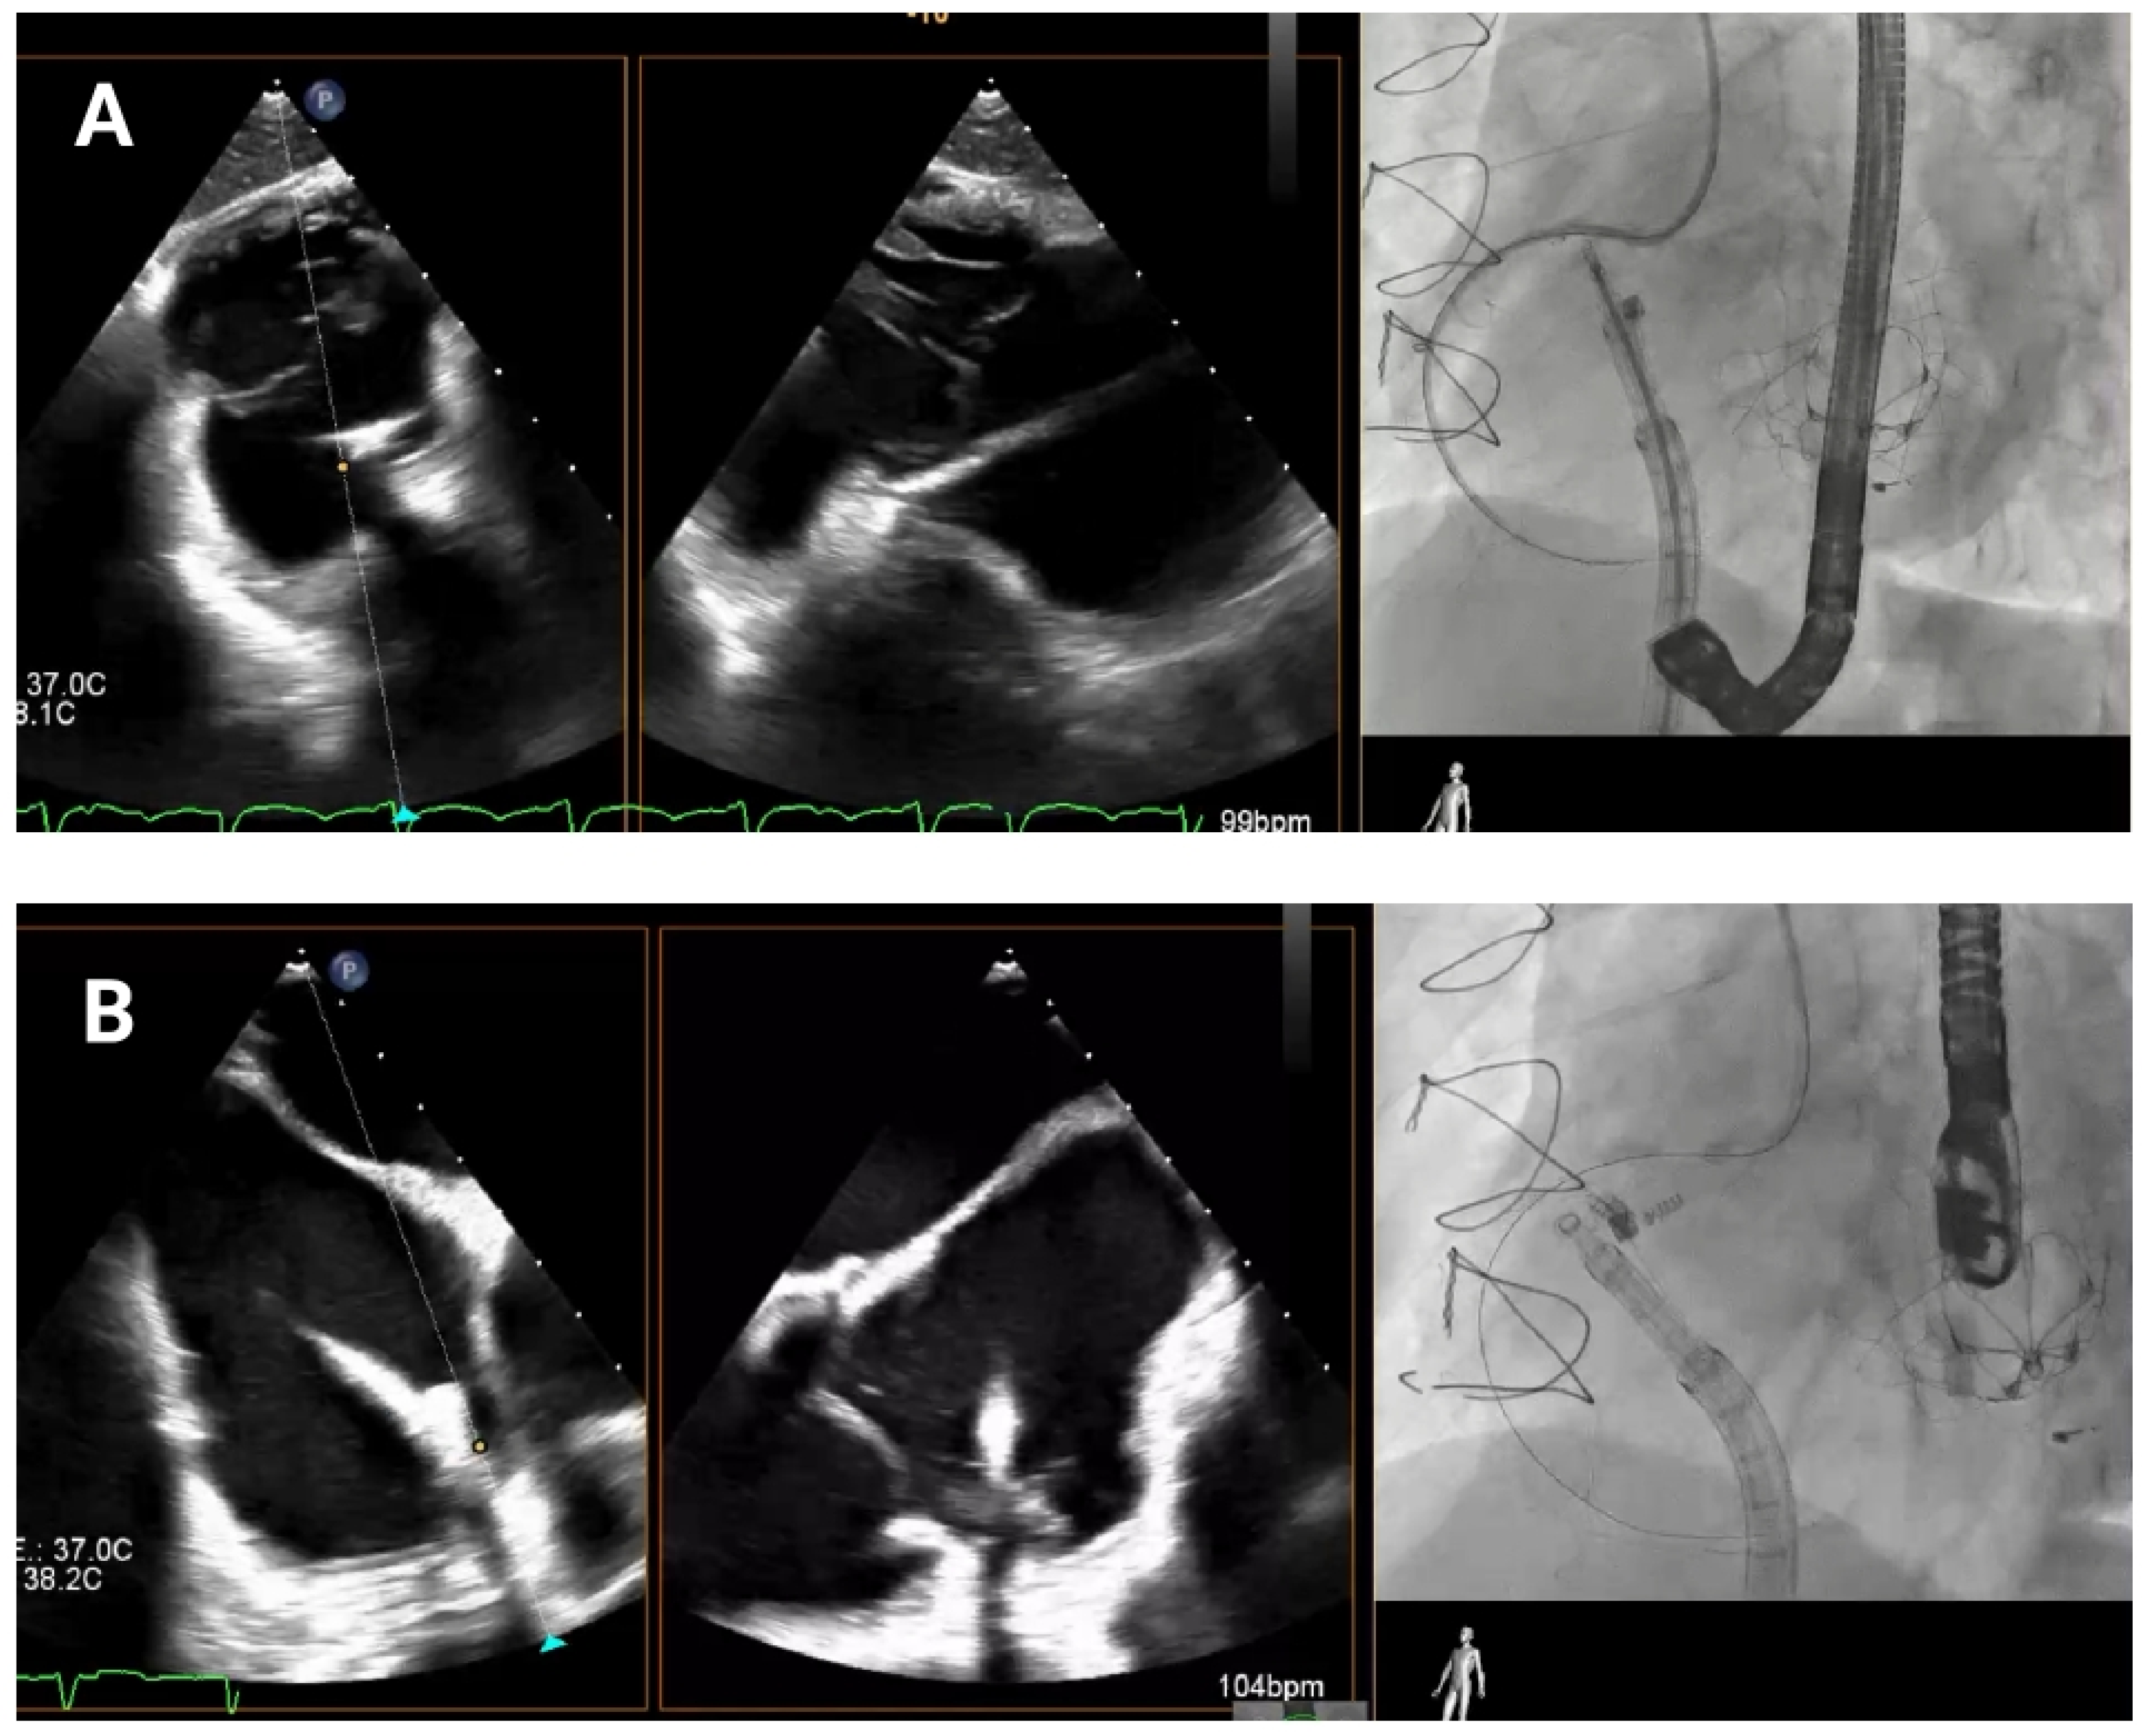

As the guide catheter approaches the tricuspid valve (

Figure 4), it is important to avoid structural interference or leaflet damage. Angiographically, the left anterior oblique projection helps visualize the anteroseptal commissure of the tricuspid annulus and ensures avoidance of the RCA course. Echocardiographically, transgastric views help visualize the anterior and posterior annulus, while high, mid, and deep esophageal views are useful for assessing the lateral annulus.

After the catheter is near the anteroseptal commissure, TEE and angiographic views are used together to check the IC tip alignment as it moves towards the tricuspid annulus. RAO projections allow visualization of the IC’s approach to the annulus with respect to its surrounding anatomy in order to confirm that the catheter’s tip follows the intended trajectory towards the target anchor points and is not obstructed by the leaflet or at risk of inducing injury. TEE bi-plane views are then employed to monitor precise positioning in relation to the hinge points and to ensure that the IC makes accurate contact with the annular tissue.

Figure 4.

Delivery system navigation. The mid-esophageal bicaval view supports real-time visualization of the steerable sheath and guide catheter, while the mid-esophageal short-axis view aids in assessing the distance to the aorta. As the guide catheter nears the tricuspid valve, fluoroscopic left anterior oblique projection helps identifying the anteroseptal commissure and avoiding the right coronary artery.